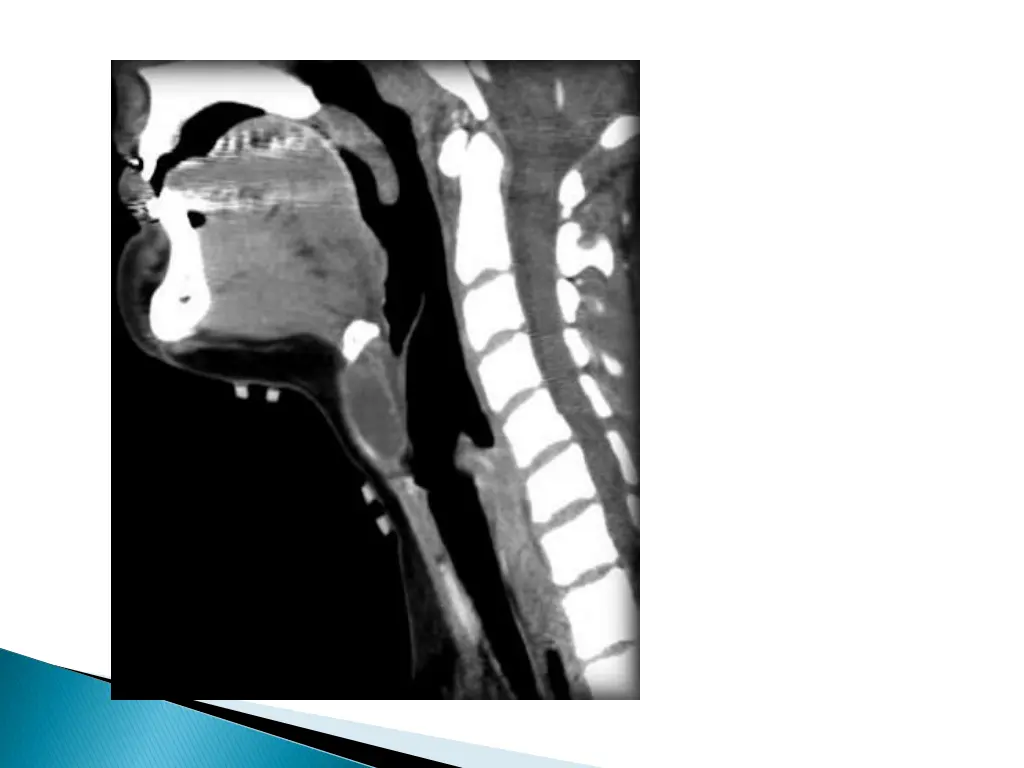

Smooth well circumscribed mass anywhere along the course of the duct. Thin walled, with peripheral rim enhancement on post contrast study. Homogenous attenuation (10-18HU). Increased attenuation suggest increased protein content and correlated with prior history of infection. Usually unilocular, occasionally septations+ Beaking of strap muscles over the surface of cyst.

CECT shows a cystic lesion in the right strap muscles.